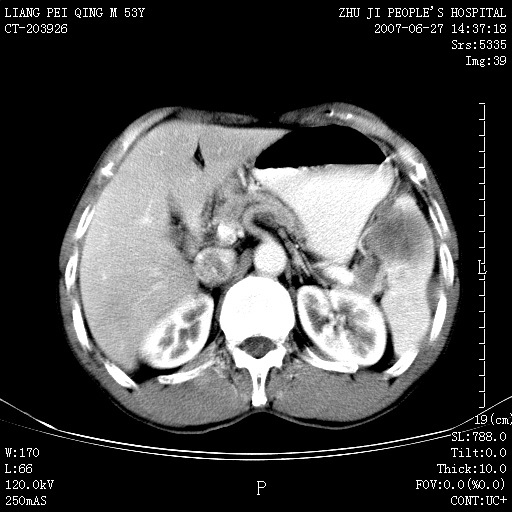

以下是引用余辉在2007-6-27 18:46:00的发言:[br]病灶多发,内可见大片状低密度区,病灶病灶等密度区轻度强化,动脉期后期病灶低密度区与高密度区对度增加,考虑1淋巴瘤2转移瘤3血管内皮细胞瘤(不知有否静脉期及延迟期扫描)

以下是引用zzzzhhhhaaaannnn在2007-6-27 20:44:00的发言:[br]脾脏 肋骨转移可能性大,下腔静脉内有癌栓

以下是引用狙击手在2007-6-28 10:35:00的发言:[br]1:定位:来源于脾脏。2:强化:强化,但不均匀。3:下腔静脉癌栓?下腔静脉充填不均匀与增强时间有关,延时即可明确。4:肋骨破坏?看起来并不确切。综上考虑几个最常见诊断:1;淋巴管瘤;2;血管内皮肉瘤(高度恶性,早期即可转移,常见肝,肺,骨)3;转移瘤(无特征性,只有肝或其它腹腔脏器有类似病变时,才可提示之)